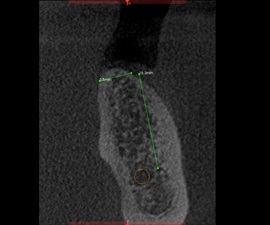

Pacjentka lat 72, od kilkudziesięciu lat chorująca na cukrzyce I typu, obecnie od 10 lat na pompie insulinowej. Profesor medycyny, siostrzenica pacjentki prowadzi swoją ciocię diabetologicznie, pacjentka świadoma zagrożeń przy zabiegach regeneracji kości i implantacji w takim ogólnym stanie zdrowia. Po rekonstrukcji tkanek miękkich i kości osadzono dwa implanty o średnicy 5,0 mm. Na zdjęciu śródzabiegowym widać zadowalające wyniki rekonstrukcji tkanki kostnej. Po upływie kilku miesięcy wykonano nadbudowę protetyczną.